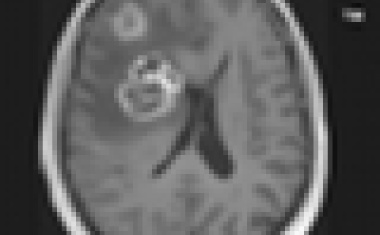

In Labortests Wachstum von Hirntumor-Zellen gestoppt und resistente Zellen für Chemotherapie erschlossen.